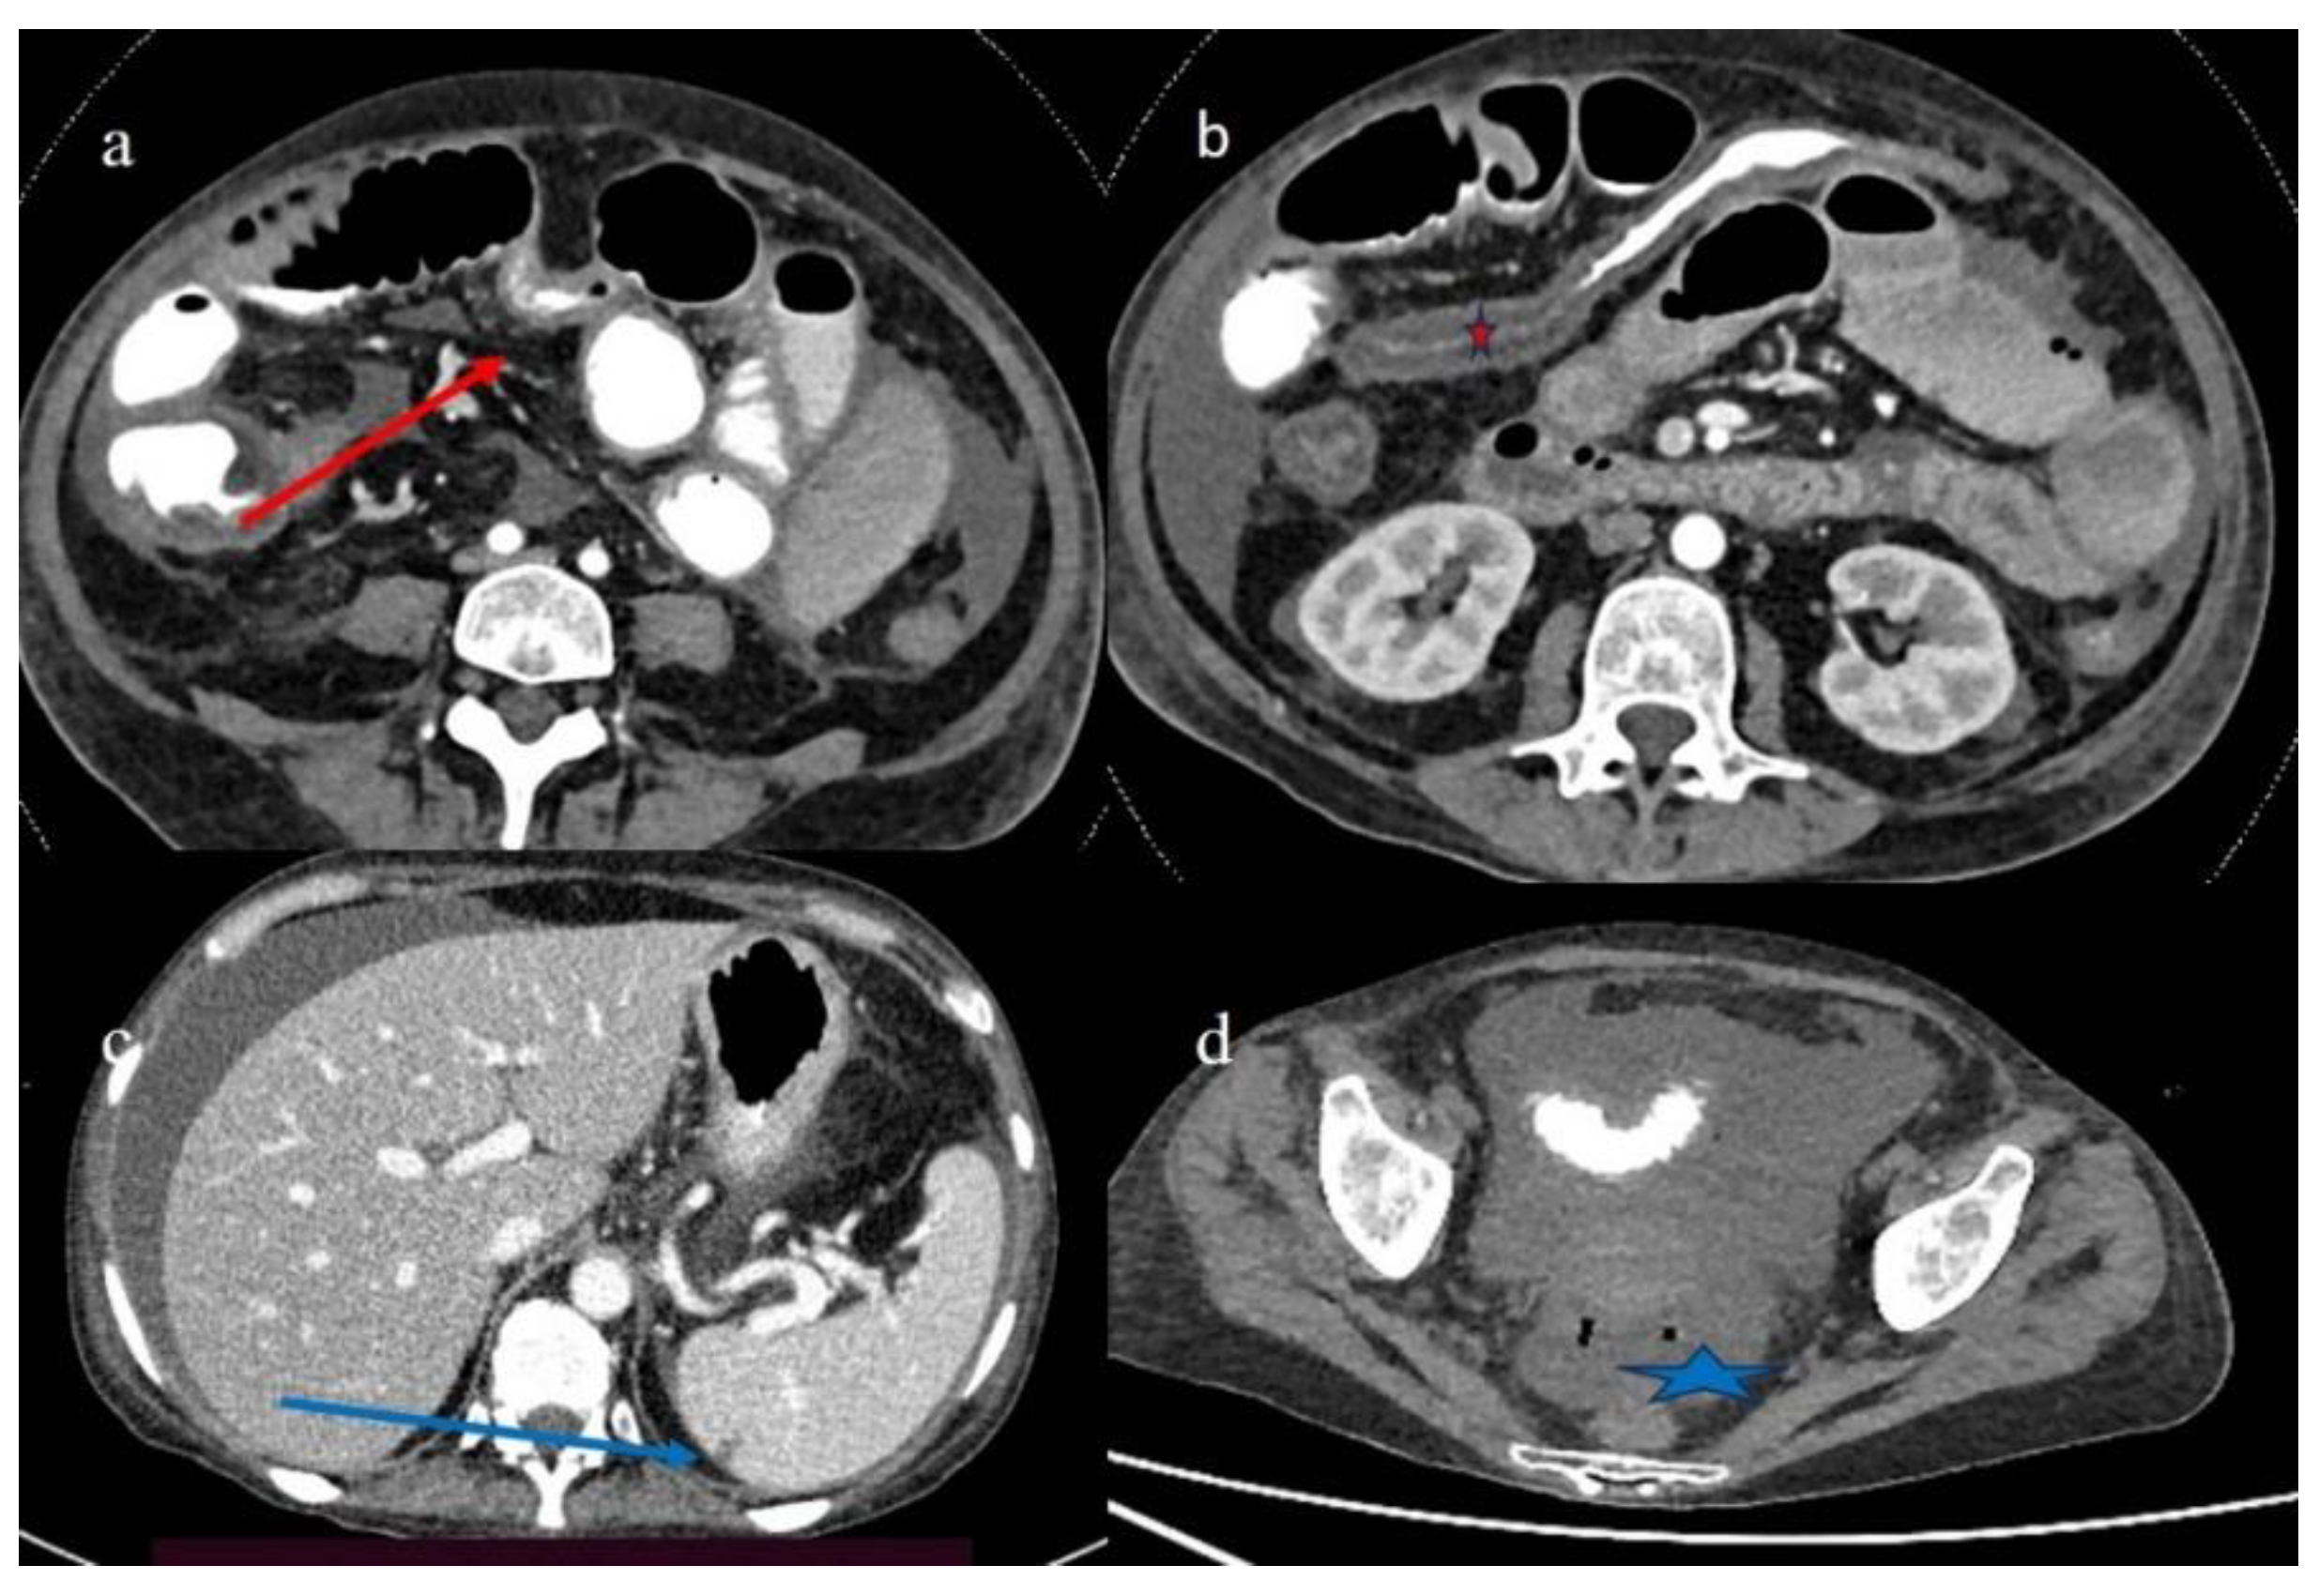

| 2 | P | P | Diffuse parietal thickness with stratified enhancement | Multisegmental thickness with homogeneous mucosal enhancement | Diffuse comb sign and poor reactive mesenteric lymph node | Mild gallbladder thickness and mild biliary tract dilatation |

| 3 | P | P | Multisegmental thickness with stratified enhancement at the terminal ileus (on CECT control at 92 days). The CECT control at 129 days showed persistence of mild parietal thickness at terminal ileus and with mucosal enhancement | Diffuse parietal thickness with stratified enhancement (On CECT control at 92 days) The CECT control at 129 days showed colic fluid distension with mild diffuse mucosal enhancement | Diffuse comb sign, mild ascites, and poor reactive mesenteric lymph node | Hepatomegaly and mild gallbladder thickness |

| 4 | P | P | Intestinal diffuse homogeneous thickness with homogeneous mucosal enhancement (on CECT control at 66 days after the HSCT); diffuse small bowel involvement with increased parietal thickness on CECT control at 120 days | Appearance of multisegmental thickness on sigma and descending colon and stratified enhancement on transverse colon on the CT FU at 120 days | Diffuse comb sign and poor reactive mesenteric lymph node | Mild gallbladder thickness and persistence of biliary tract dilatation on follow-up CT |